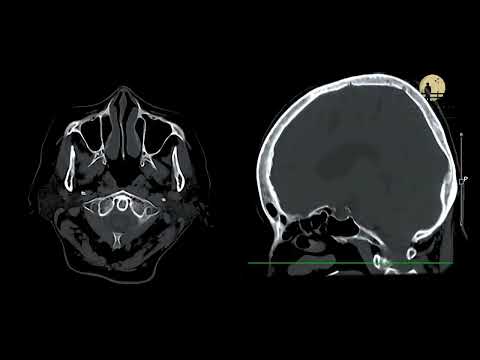

AI in clinical imagery

Tumor detection AI trained on narrow datasets can miss cancers in underrepresented populations—healthcare algorithms need the same gold-standard validation and monitoring as life-saving drugs.